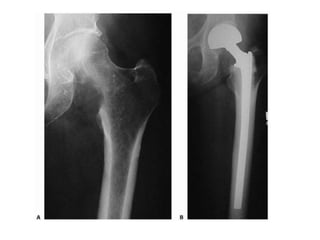

• Lower Extremity

• Acetabular – reconstruction with appropriate

prosthesis

• Femoral neck – hemi- or THR. Cemented. Long stem

• Intertrochanteric – recon nail or prosthesis > DHS

• Sub trochanteric – locked IM nail

• Femur shaft – locked IM nail preferably cephalo-

medullary

• Around the knee – locked plating > retrograde nailing